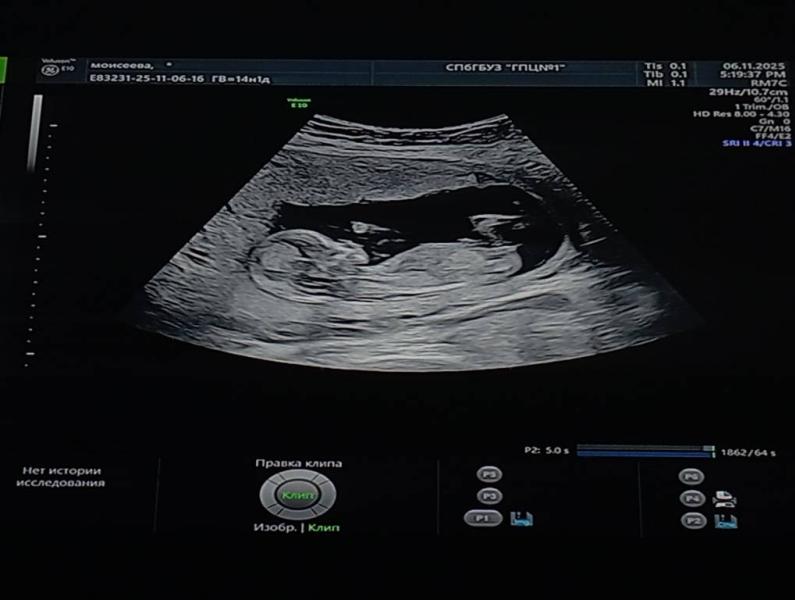

Показывала мне - вот лицо, носик, челюсть, вот спинка, ручки, ножки 🥰

Сказала, что вертлявый малыш 🤣 не хочет показываться)

Срок чуть больше, 13 недель 2 дня) Я уже переставила здесь.